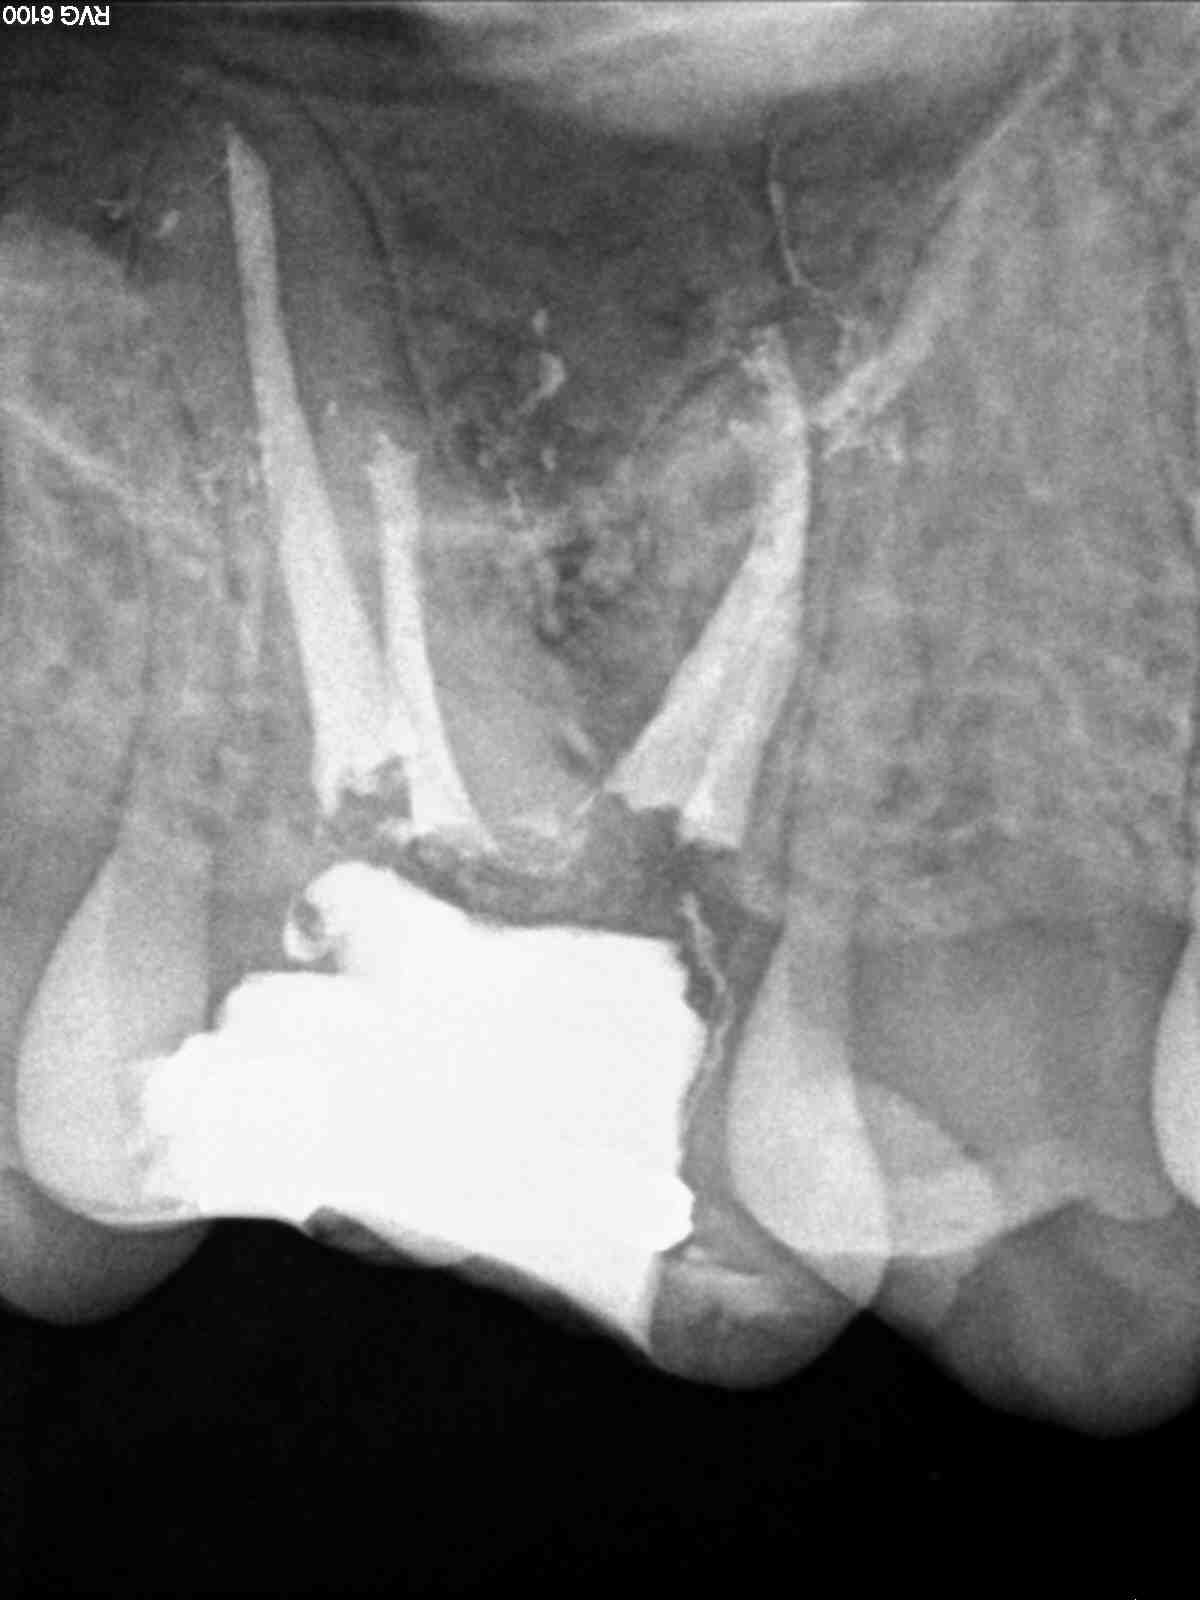

A)  Nos encontramos con un 1.7, con una necrosis pulpar con afectación periapical.

A)